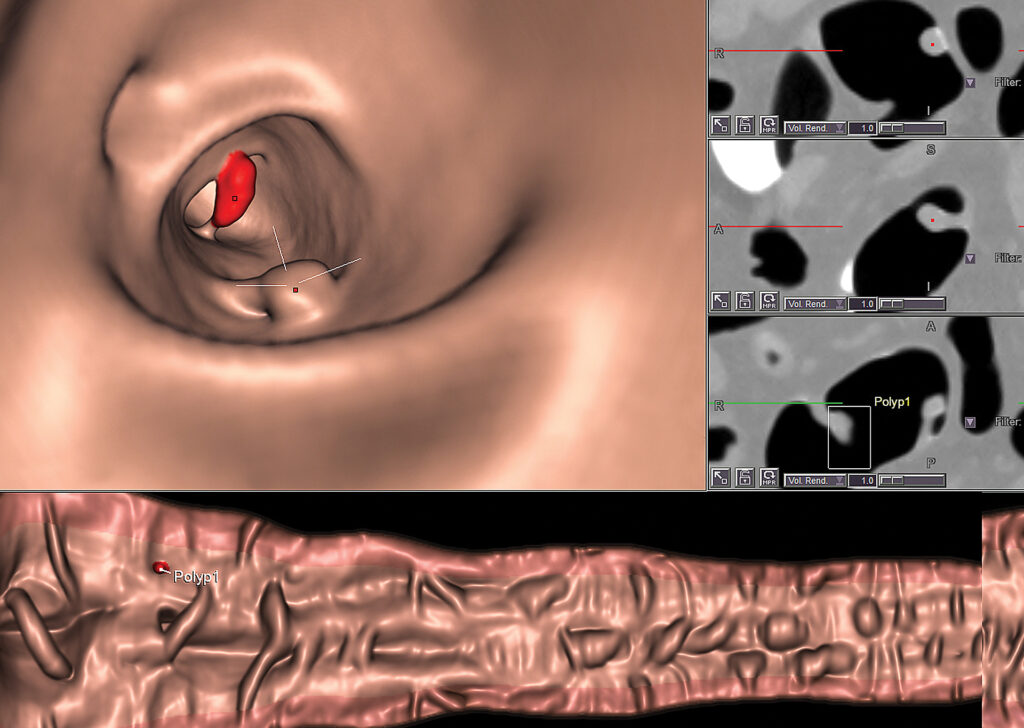

CT Colon Analysis

CT Colon Analysis provides clinicians with the ability to perform CT colonography. It provides optimized layouts for 2D and 3D examination of the lumen, including tools for quantitative analysis of suspected polyps.

iCAD VeraLook® CT Colon CAD

iCAD VeraLook CT Colon CAD uses sophisticated image processing software to identify colon polyps in CTC images, which can help to streamline the reading process and improve workflow for radiologists while supporting greater accuracy, consistency.